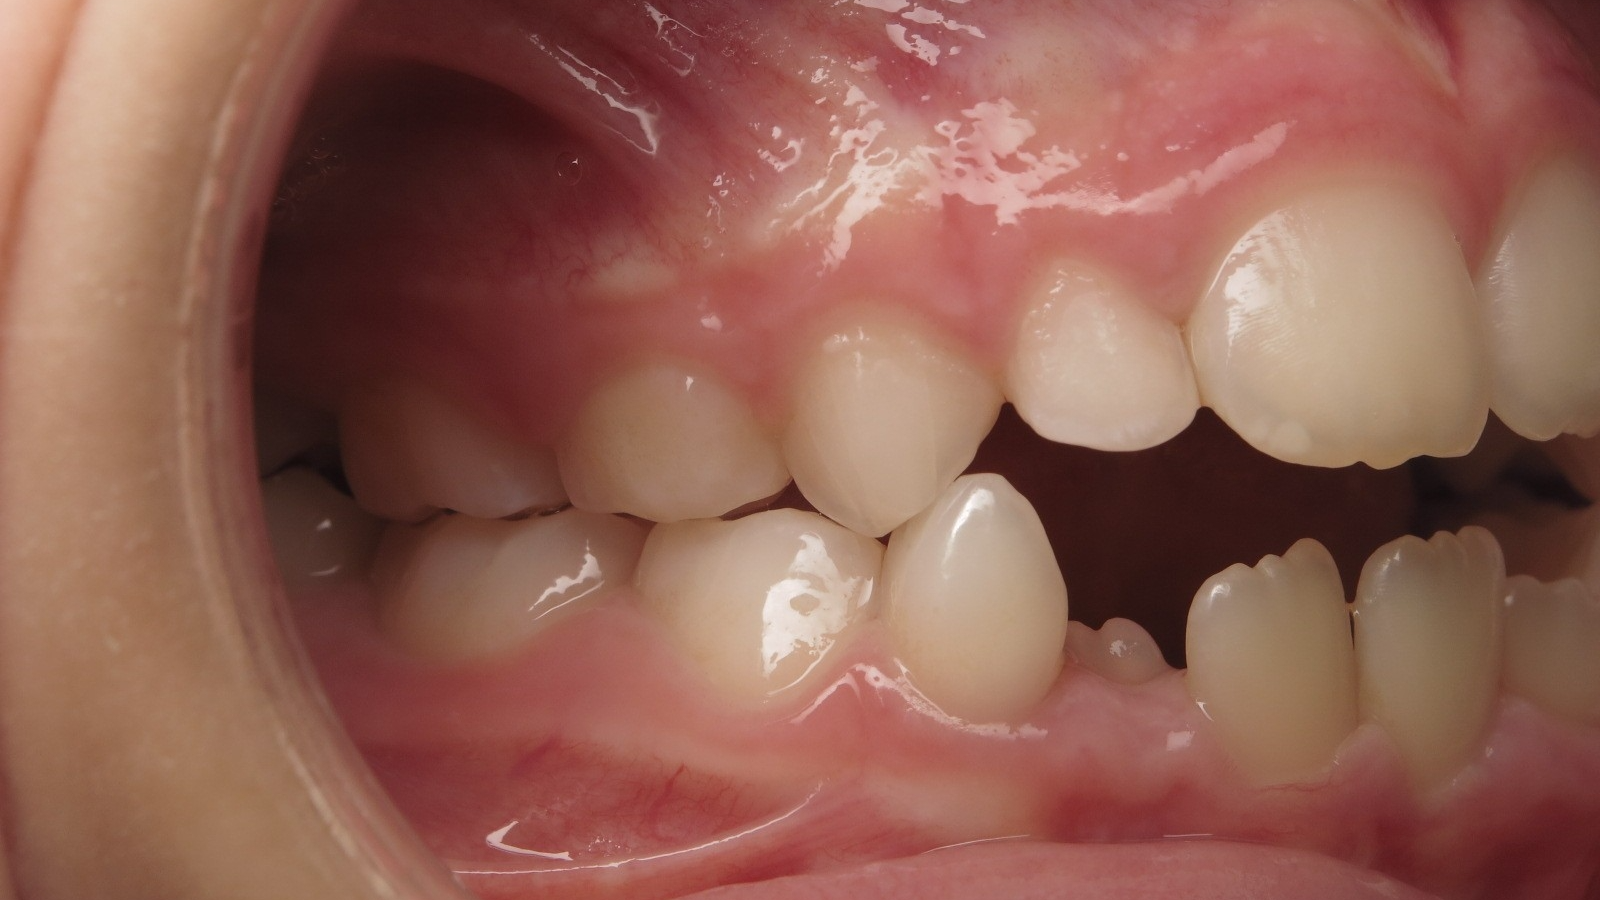

Sélectionnez les différentes étapes du traitement pour comparer et analyser la dentition du cas clinique.

appareillage mobile pendant 5 mois

surveillance évolution de la dentition pendant 27 mois

appareillage mobile pendant 14 mois